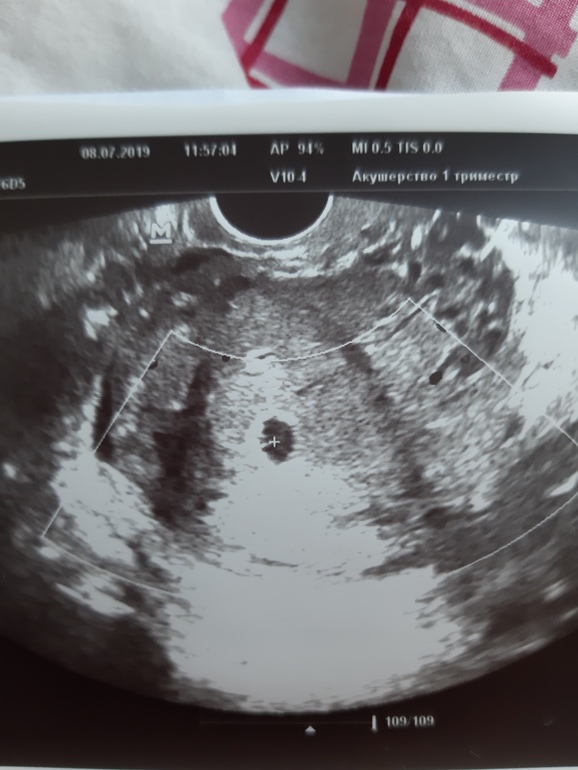

Наше узи в 5.2 недели

Ну и у нас все ттт хорошо, малыш один, сидит в дне матки очень высоко, плодное яйцо 10мм, желточный мешочек 3мм, рубец состоятельный, тонуса и отслоек тттт нет. Через недельку схожу послушаю сердечко и ходим дальше.

Ну и на фото яичко и желточный мешочек, где +